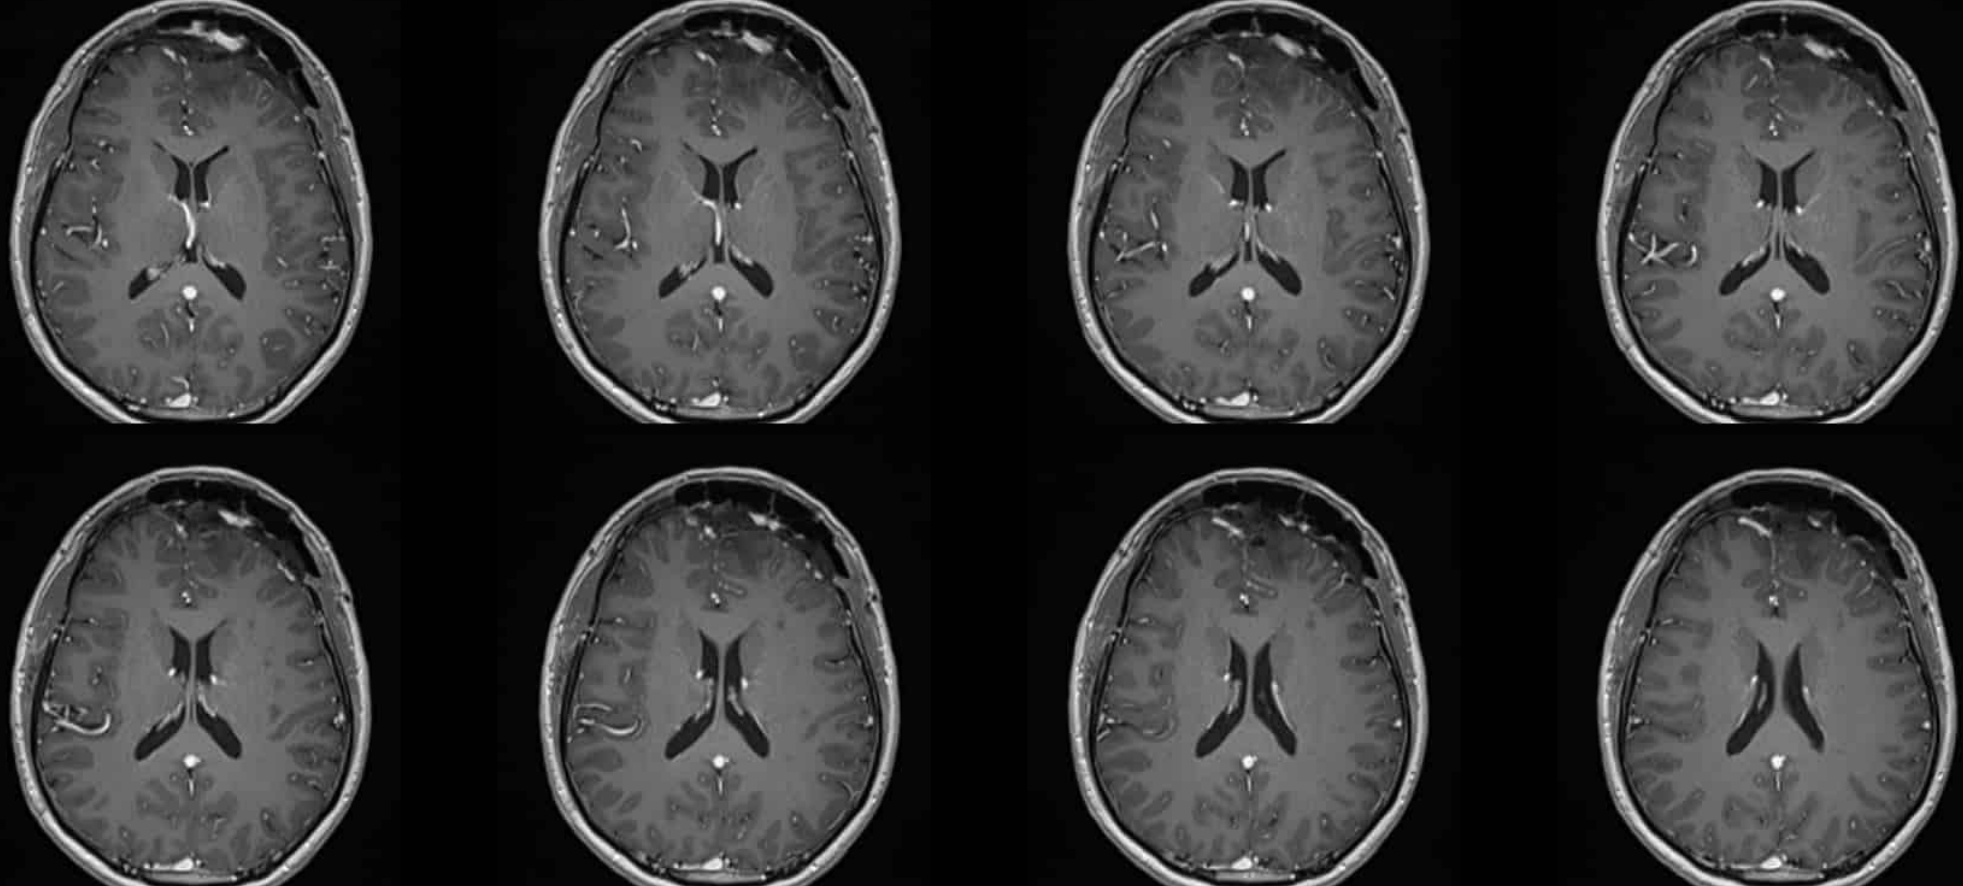

MRI

術后頭顱MR:腫瘤全切